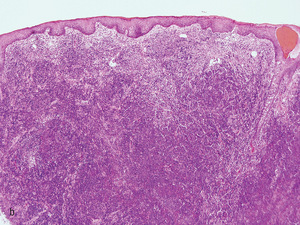

Rycina 2. (a) Badanie histopatologiczne blaszki charakterystycznej dla ziarniniaka grzybiastego ukazuje gęsty naciek komórek jednojądrzastych w obrębie górnej warstwy skóry właściwej. (b) Badanie histopatologiczne guza w przebiegu ziarniniaka grzybiastego ukazuje znaczny i rozległy naciek komórek jednojądrzastych bez cech epidermotropizmu. (c) Analiza polimorfizmu konformacji jednoniciowych fragmentów DNA. Na żelu poliakrylamidowym stwierdzono obecność klonu limfocytów T w obrębie skóry i poliklonalność krwi obwodowej.

– badania histopatologicznego (ryc. 2a i 2b)